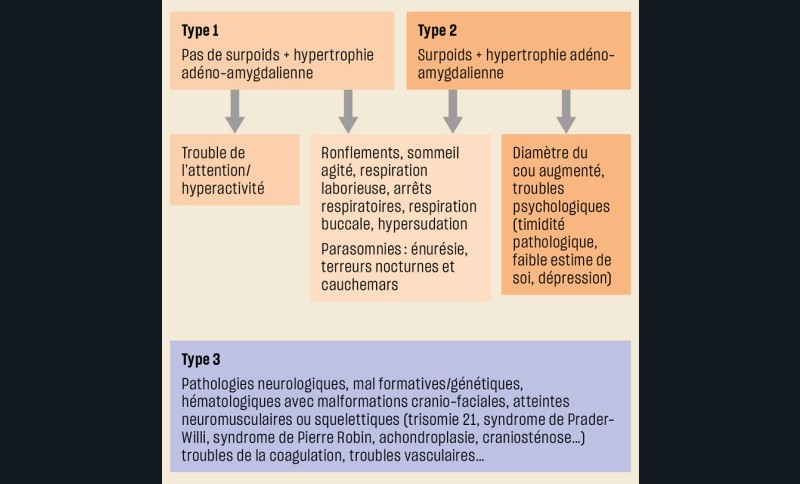

On distingue classiquement trois catégories d’enfants pouvant avoir un Sahos : les enfants sans comorbidités ou pathologies prédisposant au Sahos, les enfants obèses, les enfants ayant une pathologie pouvant être responsable de la survenue ou de l’aggravation d’un Sahos ou encore représentant un facteur de risque opératoire (fig. 1). Sont recherchés chez l’enfant, en plus des symptômes et signes d’une éventuelle maladie sous-jacente ou d’une comorbidité, des symptômes évocateurs nocturnes et diurnes (tableau 2, fig. 2). On retiendra qu’il est exceptionnel pour un enfant :

Selon que l’enfant ait ou non un obstacle ORL, soit âgé ou non de plus de 3 ans, et présente des comorbidités ou des pathologies associées, la démarche d’investigation d’un Sahos clinique n’est pas la même (fig. 3). Cependant, dans tous les cas, cette démarche repose sur l’évaluation précise de l’existence ou non d’un obstacle ORL par un médecin familiarisé à l’examen des enfants.